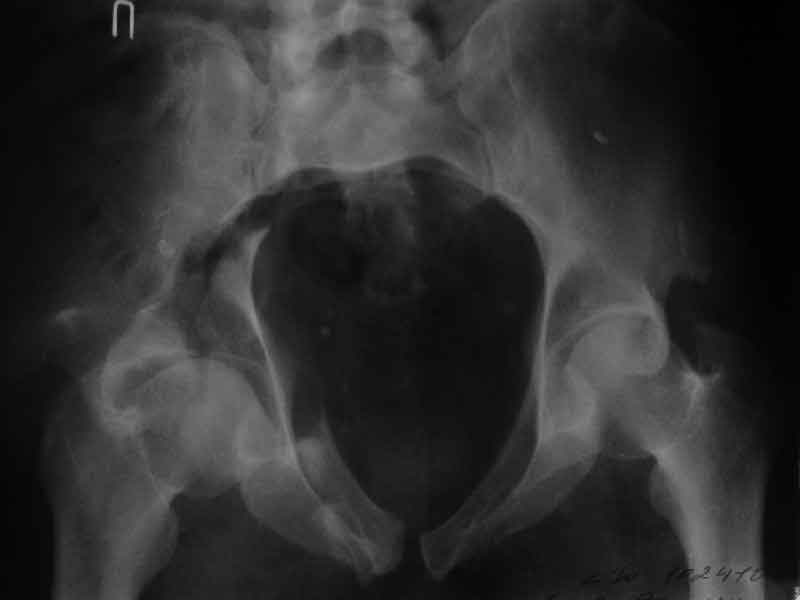

Досылаю рентгенограмму

> Досылаю рентгенограмму

Бессмысленно заниматься лечением повреждений вертлужной впадины по такой рентгенограммам, попытайтесь вправить вывих и отправить в лечебное учреждение, где занимаются лечением подобных повреждений.

Поверьте, ни в коем разе не хочу Вас обидеть, но если нет возможности сделать качественные рентгенограммы в нескольких проекциях, то грамотное лечение таких повреждений практически невозможно.